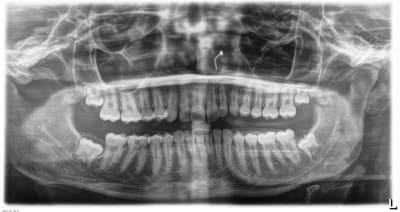

Et pour ceux qui me demandaient la pano de l'année précédente, exactement 1 an et 3 mois précédemment, la voici.

Vous pourrez comparer l'évolution rapide de la tumeur bénigne qui a refoulé les structures en les soufflant.